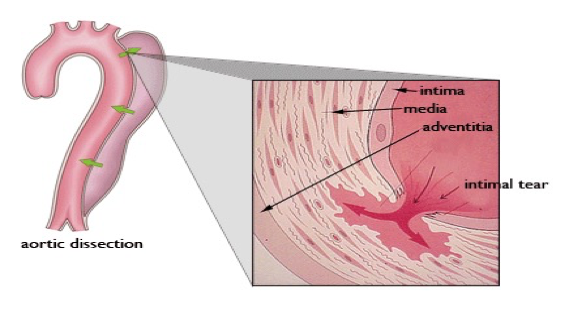

Aortic dissection

Tear in the inner wall of the aorta (intima) causes blood to flow into the middle layer (media) and force the layers apart

Aortic dissection

What does this refer to

Etiology/Pathogenesis/Risk Factors Aortic Dissection

What does this refer to (in terms of aortic dissection)

Most simplified classification system EVER!

Stanford system divided into:

Stanford Type A (proximal)

_______________

Involves the Ascending aorta

What does this refer to (in terms of aortic dissection)

Most simplified classification system EVER!

Stanford system divided into:

Stanford Type B (distal)

__________

Does NOT involve the ascending aorta